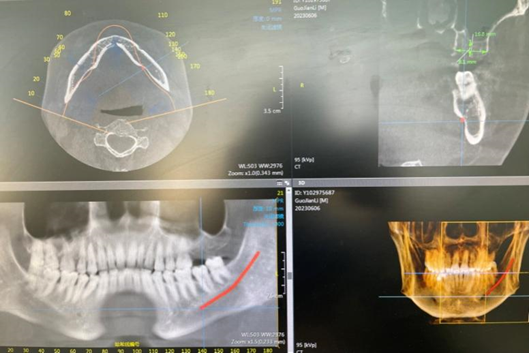

CBCT为三维成像,能提供的口腔内信息更为详细准确。它可以更加立体地观察多生牙、阻生牙的位置及周围组织结构。而且可用于种植手术前,确定牙槽骨的宽度、高度以及与上颌窦底、下齿槽神经管的位置关系,选择相应的种植体及手术方式,以达到最佳种植效果。